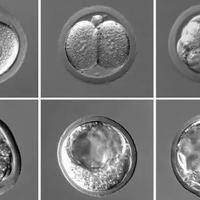

在辅助生殖技术日益成熟的当代医学实践中,囊胚移植已成为提升试管婴儿成功率的关键环节。囊胚质量评估体系通过字母与数字的组合,为胚胎发育潜能提供了标准化描述。其中,“6bb囊胚”作为常见评级之一,常引发患者对移植难度与成功率的关切。本文将围绕“6bb囊胚移植难度很大吗”这一问题展开探讨,从囊胚质量、移植技术、个体差异等多角度分析,帮助读者全面了解这一话题。囊胚分级与移植难度的关联囊胚分级是评估胚胎质量...

“3BC”作为一项常见的囊胚评分结果,常常引发准父母们的深切忧虑:“移植这样的胚胎,成功后孩子会不会不好?”事实上,囊胚评分是一个基于形态学的动态评估体系,它主要反映胚胎在特定时间点的发育状态和着床潜力,而非对其未来个体健康与智力的直接判定。本文将深入解析“3BC”评分的具体含义,探讨其与临床妊娠成功率及子代健康的内在关联,旨在为准父母提供科学、客观的认知视角,缓解不必要的焦虑。囊胚质量与胎儿健康...

4ab囊胚移植成功率,受多因素制约但个性化方案可提升妊娠率

在辅助生殖技术日益成熟的今天,囊胚移植已成为提高试管婴儿成功率的关键环节。其中,4ab囊胚作为优质囊胚的代表之一,其移植成功率备受关注。根据国际囊胚分级标准,4ab囊胚指的是处于扩张期、内细胞团和滋养层细胞均表现良好的优质囊胚,这类囊胚在临床实践中通常展现出较高的着床潜力。本文将系统解析4ab囊胚的特点、移植成功率及其影响因素,帮助正在接受辅助生殖治疗的家庭更全面地了解这一重要环节。4ab囊胚移植...

4aa囊胚移植成功率,着床率一般可达60%-70%

在辅助生殖技术领域,囊胚质量是影响试管婴儿成功率的核心因素之一。其中,4aa囊胚作为顶级优质囊胚的代表,其移植成功率备受关注。根据国际通用的Gardner囊胚分级标准,4aa囊胚指的是处于扩张期、内细胞团和滋养层细胞均评级为a级的优质胚胎,这种囊胚在形态学上表现出卓越的发育潜能。本文将系统解析4aa囊胚的特点、成功率数据及其影响因素,为接受辅助生殖治疗的患者提供全面参考。4aa囊胚移植成功率解析在...